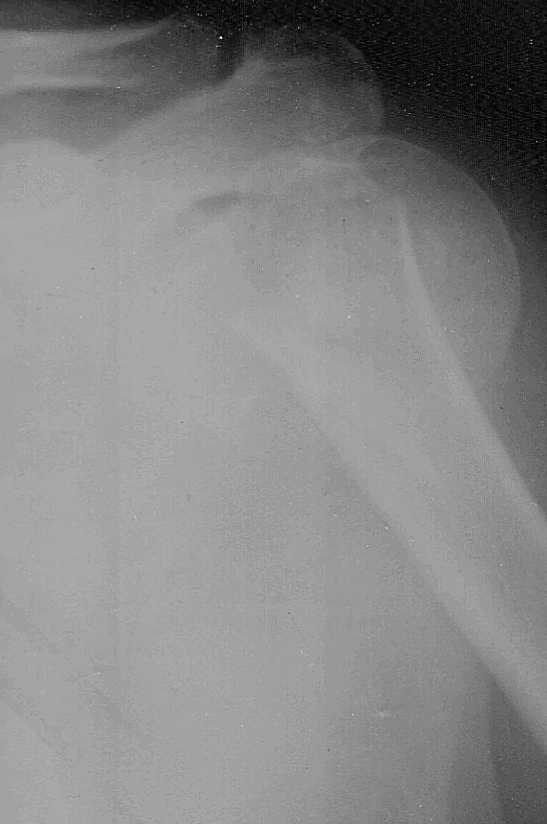

Доброго времени суток,коллеги.Больная 51 год травма 2,11,09 в 20:00 сосудистых,неврологических расстройств нет

3,11,09 выполнена попытка закрытой репозиции,безуспешно. Планируем накостный синтез Т-образной пластиной.Буду крайне признателен за дельные советы.